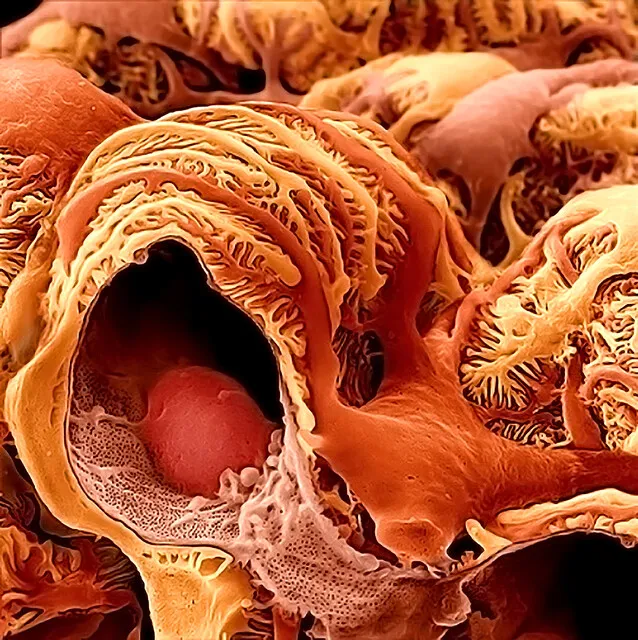

Intoxicação por citrato na contínua: quando suspeitar e como tratar

Intoxicação por citrato na contínua: quando suspeitar e como tratar